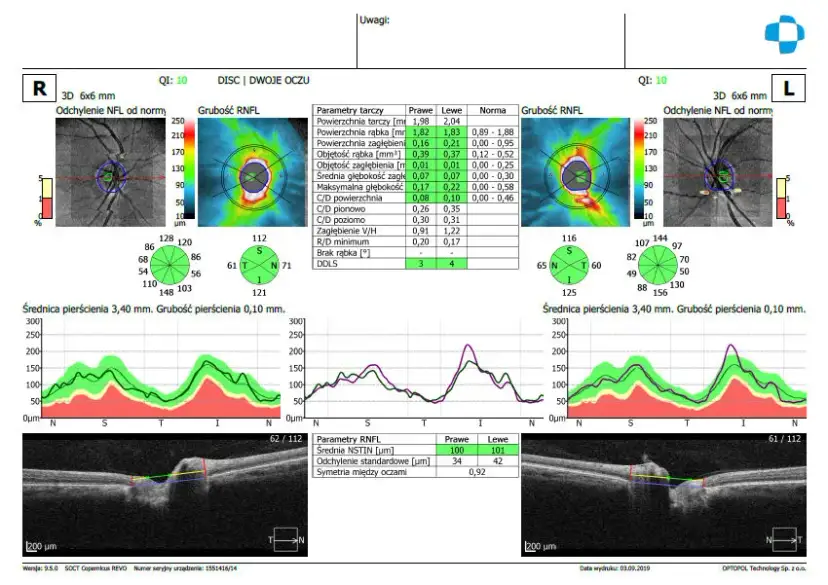

Badanie OCT: dowiedz się, czym jest ta precyzyjna tomografia oka, jak przebiega, co diagnozuje (jaskra, AMD) i ile kosztuje. Sprawdź nasz przewodnik!